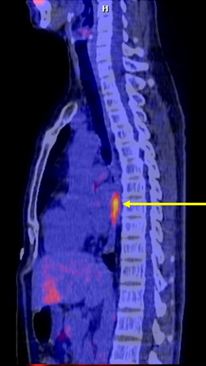

Bệnh nhân được chụp PET/CT để đánh giá giai đoạn và mô phỏng lập kế hoạch xạ trị:

Hình 2: Hình ảnh chụp PET/CT: có khối u ác tính ở 1/3 giữa thực quản với kích thước 1´0,8´4cm,tăng hấp thu FDG, max SUV=4,64, không có hạch, không có di căn xa

Chẩn đoán xác định: Ung thư­ thực quản T2N0M0.